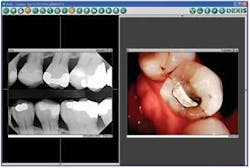

Whether you have a moderately priced or high-end intraoral or digital still camera, you and your team should take time to integrate it into your routine work flow. Make it a habit to capture camera images like you do X-rays. Just as an enlarged digital X-ray gets your patients’ attention and lets them see their condition, so do camera images.

After you’ve captured pictures, what do you do with the images? Don’t keep them to yourself! We show them on a 42-inch monitor that swings out from the wall to face the chair. You can do the same - show patients the images on your computer monitor.

These visuals are especially important with new patients with whom you haven’t had time to build solid relationships. When faced with the evidence of X-ray and camera images, patients feel sure you are suggesting treatment they really need. There’s no second-guessing your recommendation - patients essentially diagnose themselves!

What about after treatment? Don’t stop with a “before” picture; share the “after” image with your patients, too. Never miss the opportunity to print out images for patients to take home and share with family and friends. These pre- and post-treatment images remind patients of their previous conditions and how you were able to restore the area. The message is clear: “We deliver on our promises, and you can trust us.”